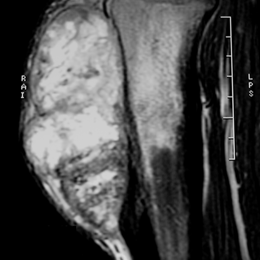

24C) Sag MR T2 Periosteal Osteosarcoma

Radiographic imaging is used to help form a diagnosis. These include X-Ray, MRI, CT and Bone Scans